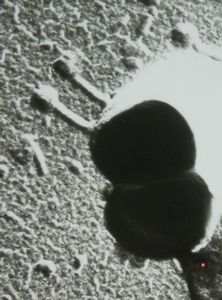

staphylococcal bacteriophage